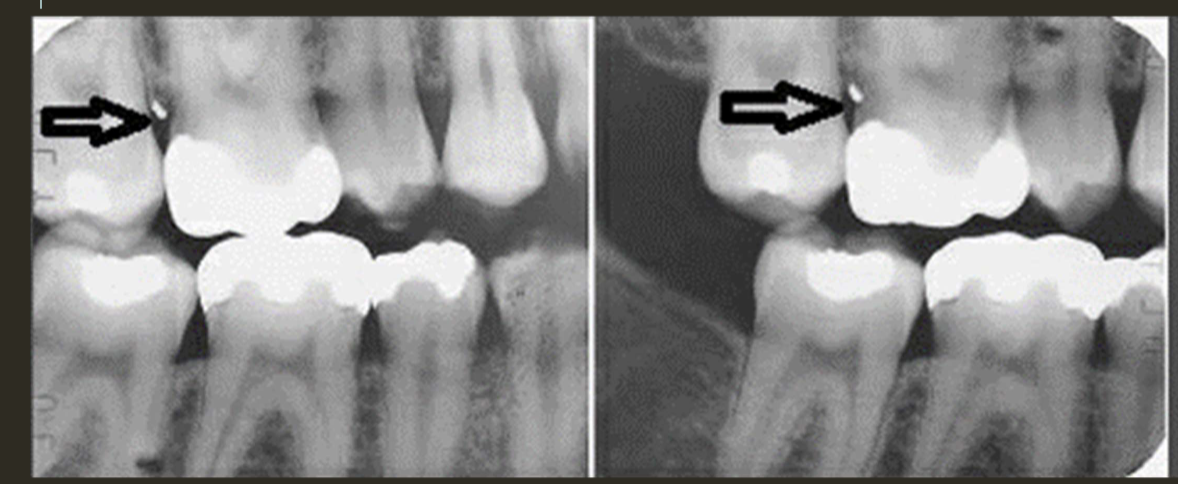

buccal object rule

expose 1st image (PA or bw)

take a second image with a different H or V angulation aka same area different angle

compare images to see how the object shifted in the image

SLOB

lingual

right angle technique

buccal

lingual

lingual

buccal